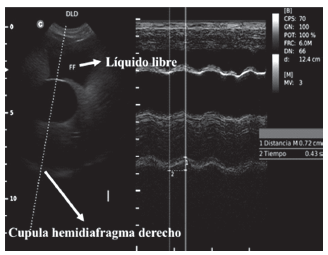

Perros internados

Un total de 33 perros que se incluyeron inicialmente en el grupo de internados, en base a los hallazgos del examen clínico y ultrasonido de pulmón y corazón. Se excluyeron perros con patrón de respiración restrictiva con signos de patrón nodular pulmonar bilateral (n = 1) (Fig. 7), aumento en el tiempo inspiratorio, que no permitió identificar bien la onda para la toma de medidas (n = 1), fluido libre abdominal y movimientos diafragmáticos disminuidos, shock séptico (n = 1) (Fig. 8). El total de los perros tenían entre 1 - 12 años y entre 2,5 y 50 kg de peso.